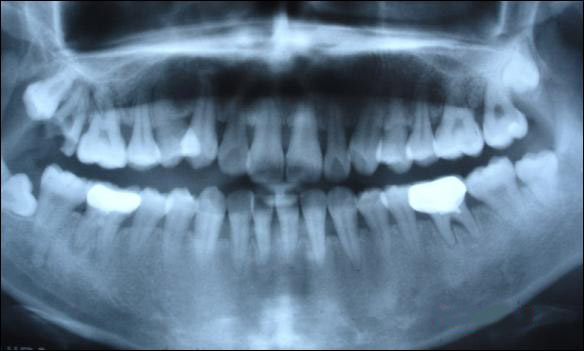

上圖為健康人的全口曲面斷層片,俗稱骷髏片

從上圖可以看出,牙槽骨被吸收,牙齦萎縮,牙縫變大